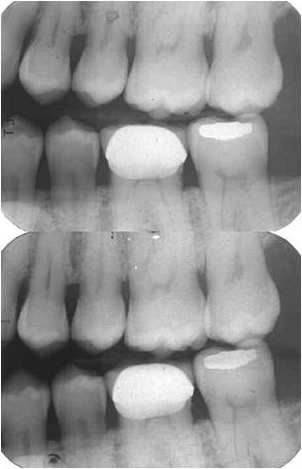

Today D- and E-speed films are virtually identical in image quality. When E-speed film was first introduced the image quality was somewhat inferior to D-speed film which resulted in a now undeserved reputation of grainy and low contrast images. The two films below look almost identical but with a significant difference in dose. The E-speed film (top) required a dose of 120 mrad while the D-speed film (bottom) required 200 mrad. This results in a dose reduction of approximately 40% for patients and staff.